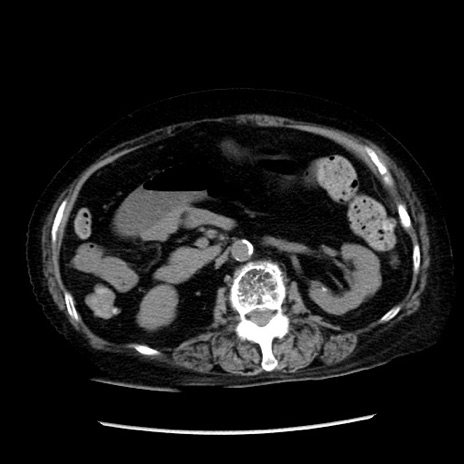

冠状断像

【症例】 90歳代女性

【主訴】 腹痛・嘔吐

【現病歴】今朝から左側腹部痛を認めた。 経過観察していたが、嘔吐を認めたため来院。

【既往歴】 子宮癌術後

【身体所見】 意識清明、BP 127/54mmHg、P 98bpm Sp02 95%(RA)、BT 35.8°C、腹部平坦・軟腸ぜん動音聴取良好、右下腹部圧痛(+) 反跳痛なし

【データ】WBC 9800、CRP 0.46